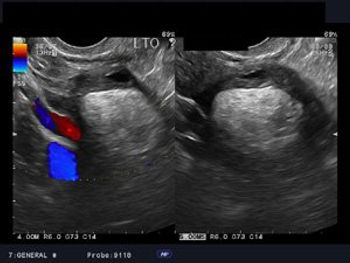

In a systematic review of UAE versus other surgical interventions for symptomatic uterine fibroids, researchers concluded that UAE offers substantial improvements in symptoms of uterine fibroids but may not help women who want to retain their reproductive potential.